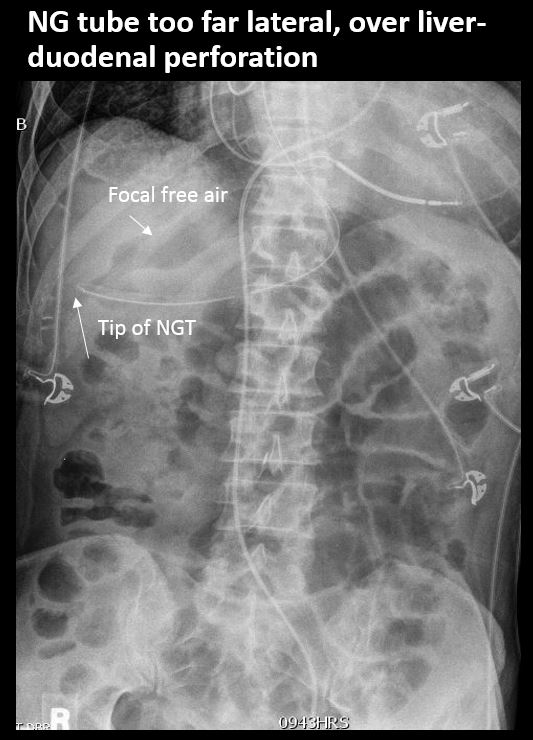

There is free air present.

There is an NG/OG/FT tube which is malpositioned.